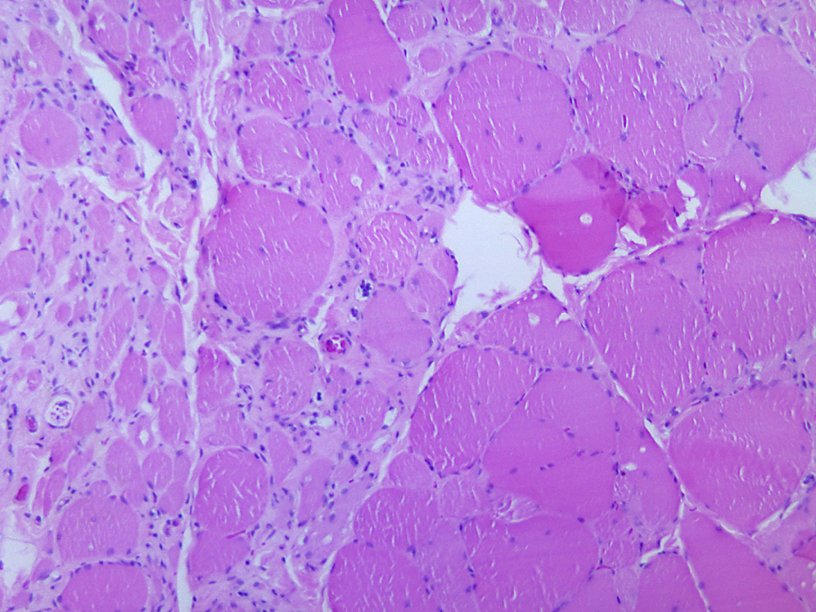

Дистрофические изменения в мышечной ткани, вызванные полиомиелитом Wikimedia Commons Обнаружена новая разновидность вируса полиомиелита, от которого не вполне защищает современная вакцина. В чем тут дело, разобралась межнациональная группа ученых. Итоги их работы опубликованы в журнале Proceedings of the National Academy of Sciences. Среди авторов исследования есть и россияне – сотрудники Института полиомиелита и вирусных энцефалитов имени М. П. Чумакова. В этом институте работает референс-центр ВОЗ по надзору за полиомиелитом.